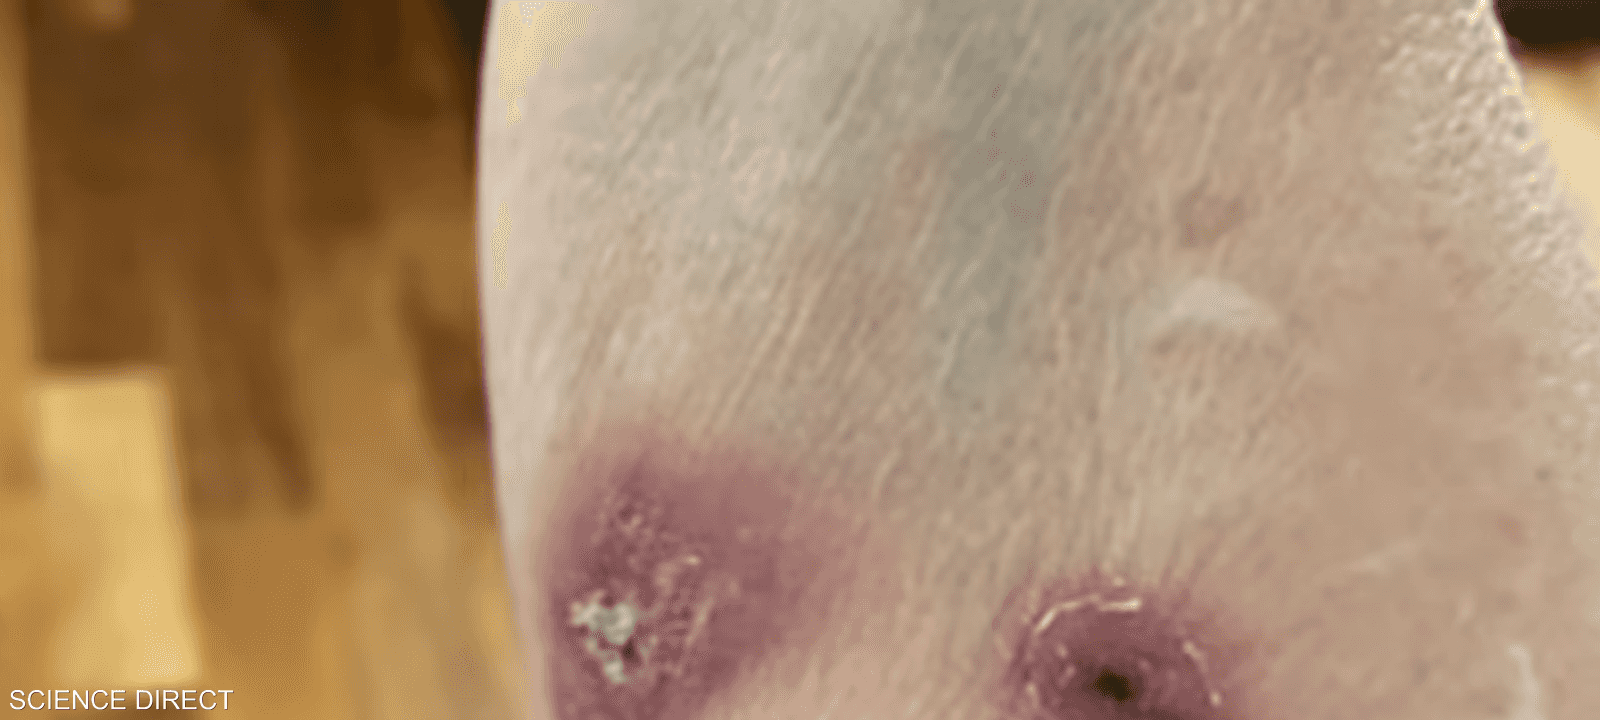

وأبلغ 3 بريطانيين عما يشبه الفطريات على الجلد، قائلين إنهم يعانون بثورا وجروحا في مناطق متفرقة في الجسم مثل اليد والمعصم والذراع.

وتبدأ أعراض المرض بظهور ما يشبه الخدوش والجروح، في المناطق التي تعرضت للعدوى بشكل مباشر.